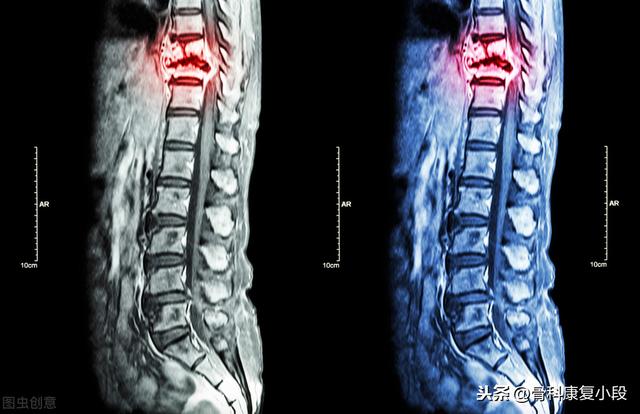

Magnetresonanztomographie von Knochenmetastasen

Nachweis von Knochenmetastasen in der Brustwirbelsäule